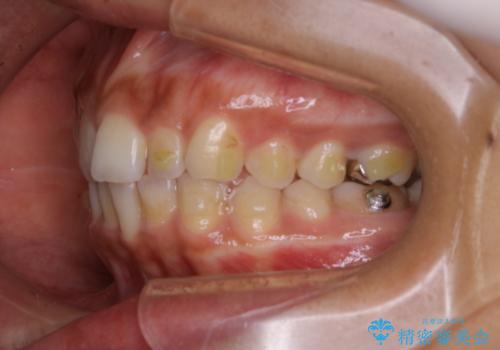

- インビザラインでの矯正治療中に、着色や汚れが気になるとのことでした。PMTC60分コースを行いました。

インビザライン治療中には、歯の表面にアタッチメント(効率的に歯の移動をするもの)を設定します。そのため歯ブラシでは届きにくい細かい部分などに、歯石や着色がついてしまうことがあります。着色などを放置していると、着色なのか、虫歯なのかの判別もしずらく正確にお口の中の状態を診断できません。